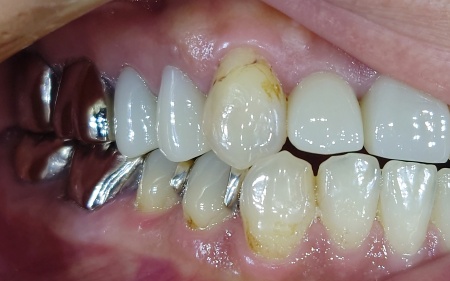

拝見したところ、右下の乳歯(第2乳臼歯)が抜けないまま、その下から永久歯が生え始めている「乳歯晩期残存」が認められました。

通常であれば乳歯は一定の時期に抜けますが、乳歯が残っているままだと永久歯が正しい位置に生えることができず、歯並びや噛み合わせに影響を及ぼす可能性があります。

また乳歯が残った状態では歯磨きがしにくくなり、汚れが溜まりやすいため、虫歯や歯周炎のリスクも高まります。